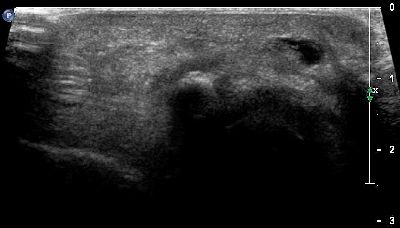

Pannicolo fibrotico intrarticolare

(caso del paziente G.V.)